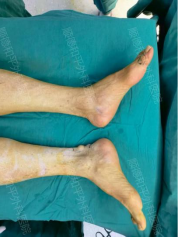

病例回顾: 患者李先生,四肢多发巨大痛风石10余年,肿物持续增大导致活动受限。此类晚期、多发性病例,若行传统开放手术,往往需要多处大切口,术后剧痛、恢复期漫长。

创伤极小: 显微技术仅需0.5-1.5厘米的微小切口,即可深入病灶区域。对李先生这样多发性的患者而言,意味着手术总创伤被降到最低,避免了因大切口对皮肤血运和神经造成的额外伤害。

恢复迅速: 得益于微创操作,患者术后当天即可在指导下下床活动,3-5天即可出院,极大地缩短了住院时间,减轻了患者的身心负担和经济成本。这对于老年患者(如65岁的李先生)尤为重要,能有效避免长期卧床可能引发的并发症。